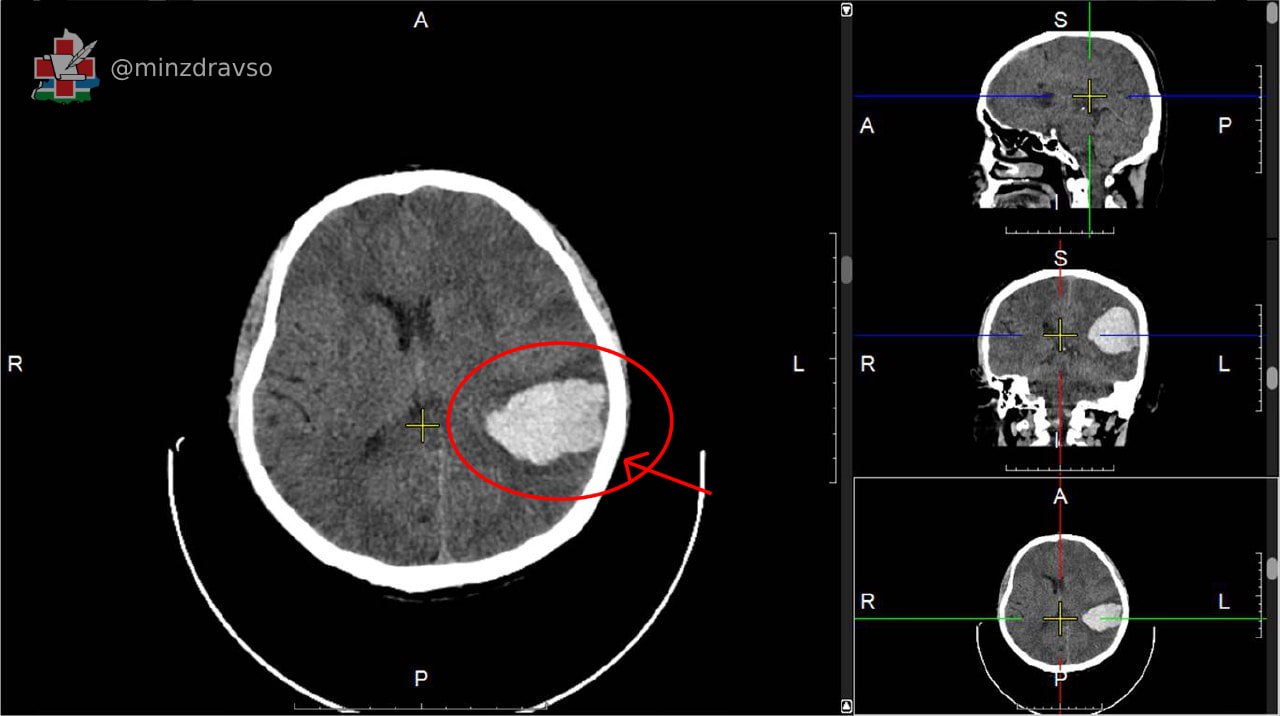

Врачи связались с коллегами из Городской клинической больницы №40 Екатеринбурга для постановки точного диагноза и выбора тактики лечения. Мужчине провели компьютерную томографию, КТ-ангиографию сосудов головного мозга, и специалисты приняли решение выполнить хирургическое вмешательство. Пациента безотлагательно доставили в Городскую больницу №1 Нижнего Тагила, где нейрохирурги удалили внутричерепное патологическое образование, полностью восстановив кровоснабжение.

После проведённого лечения у мужчины практически полностью восстановились речь и двигательная активность. В настоящий момент он чувствует себя хорошо, самостоятельно ходит, выписан из стационара и направлен на амбулаторную реабилитацию по месту жительства.